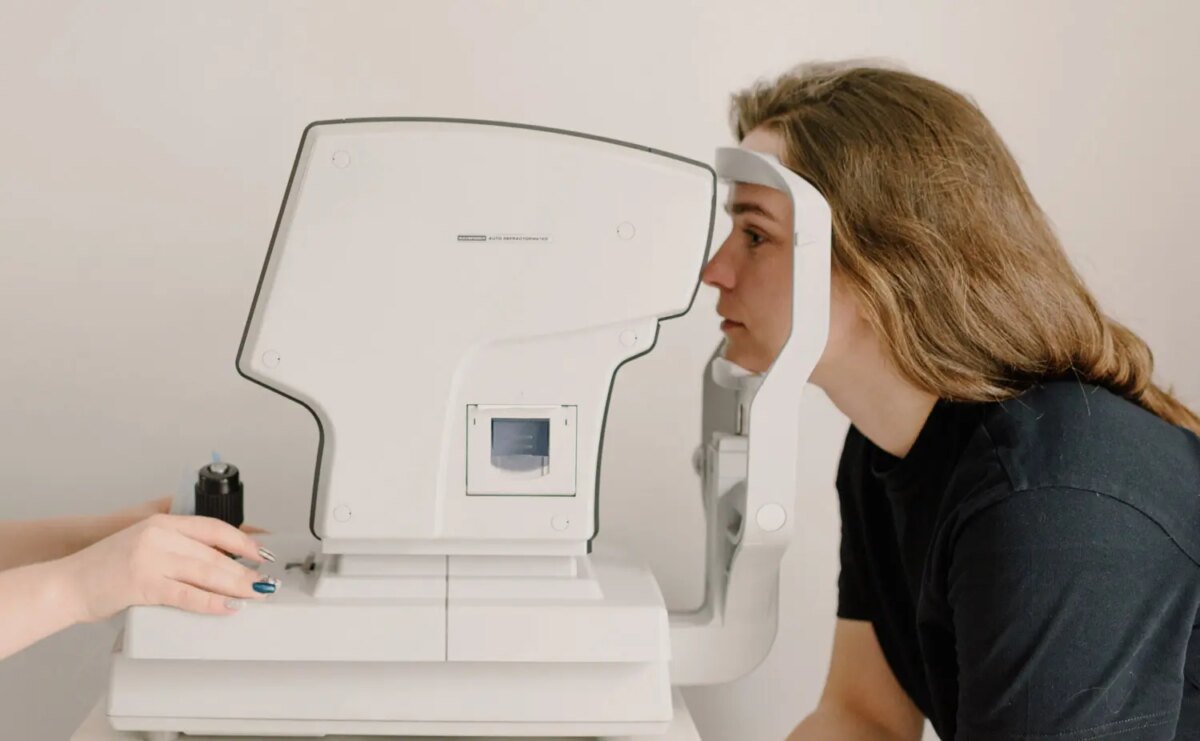

Medical Technology

The MedTech landscape is undergoing rapid transformation with the emergence of innovative devices and products, integrated platforms, and digitally powered selling and service models. At Beratung, we specialize in assisting clients in navigating these changes by helping them develop the right strategies and execute them flawlessly.